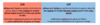

Ligaments croisés du genou :

- Trajet ?

- Fonction ?

Anatomie du genou